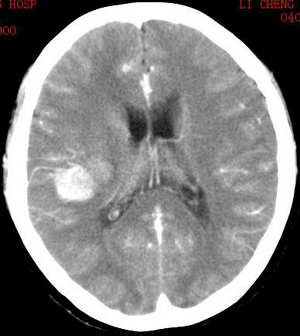

男,.40岁,头晕乏力三月余

脑皮质为主的多发结节病灶。类圆形,首先考虑脑转移瘤,平扫片病灶为高密度,增强后仍强化十分显著,常见于黑色素瘤、甲状腺癌、肾癌脑转移瘤。

在临床资料很少的情况下,就影象而言:

在考虑转移瘤的情况下千万可别忘了还有一个

与之很难鉴别的多发性海绵状血管瘤。

颅内多发结节,占位效应不明显,有几个病灶与脑膜关系密切,见强化明显,考虑多发性脑膜瘤可能!!!!

此病人已做过mr平扫加增强,我将尽快贴到网上.

病人胸片示右下肺近心膈角大片壮实变.

脑转移瘤伴出血(肺ca)

[emb6]脑内多发海绵状血管瘤一般无灶旁水肿。